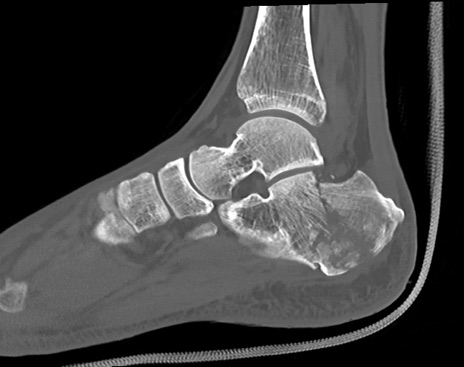

症例37 左足関節CT(矢状断像)

左足関節CT